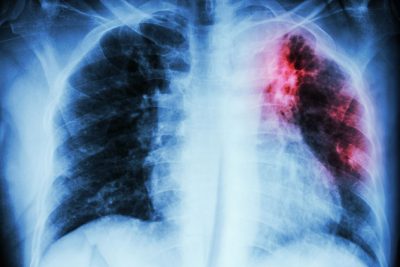

Updated Recommendations for Drug-Susceptible and Drug-Resistant Tuberculosis

Synopsis: The authors provide an update of recommendations for the treatment of tuberculosis, including cases with drug resistance. The recommendations include the use of newer drugs that have undergone clinical trials and shorter durations of therapy.

A 25-member panel representing multiple societies reviewed the 2022 World Health Organization (WHO) guideline on the treatment of tuberculosis and updated the recommendations in light of clinical trial data published since that time. The recommendations were considered for use in settings with effective relevant laboratory support. Although the update also addresses treatment of children, only treatment of adolescents and adults will be reviewed here.